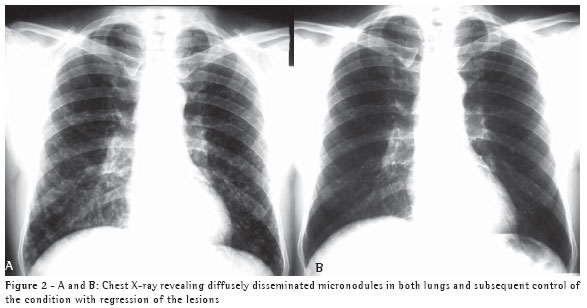

A 67-year-old white male, resident of the city of Blumenau, in the state of Santa Catarina, and a sales representative, presented with dyspnea, asthenia, chest pain, and sweats ten days after having cleaned his attic, where there are water tanks. He was in contact with bat guano for a limited period of time when the area was being swept. The presence of pulmonary nodules on the chest X-ray and tomography of the chest (Figures 1A and 1B), together with the absence of expectoration, justified the performance of a biopsy to evaluate the pulmonary nodule.

Epidemiological history can raise diagnostic suspicion. Knowledge of clinical syndromes, together with clinical suspicion, can avoid the use of empirical treatment. Radiological findings, negative test results, and the high frequency of tuberculosis in Brazil were the motivations for prescribing tuberculosis treatment for both patients. Immunodiffusion test results, although negative for these two patients, have high sensitivity and are positive in approximately 75% of cases.(6) Length of exposure determines disease severity. This explains the fact that the second patient, who was the one who swept the area, presented a more severe form of the disease, with diffuse pulmonary alterations on the chest X-ray, and required hospitalization. However, a short exposure time results in focal pulmonary lesions, as in Case 1.